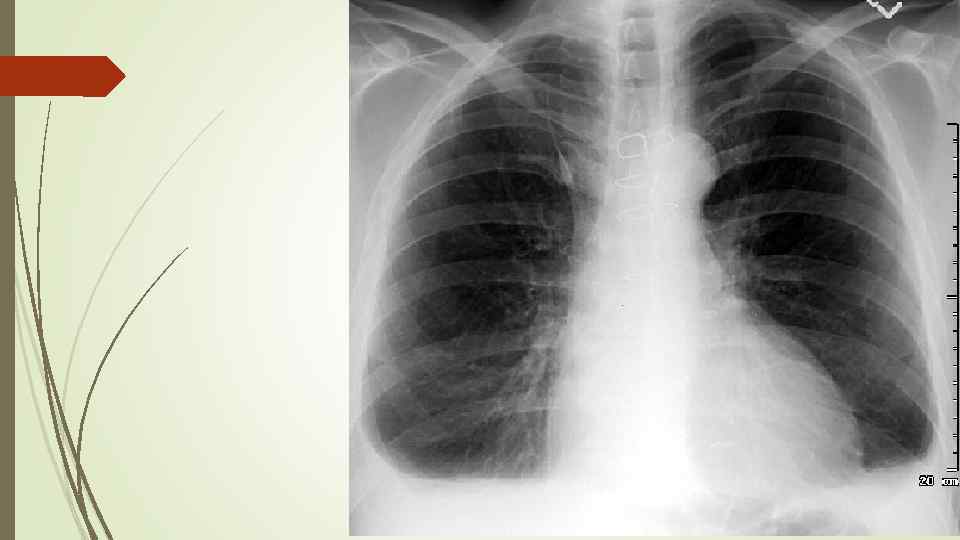

Пневмоторакс – скопление газа в плевральной полости, ведущее к спадению ткани легкого, смещению средостения в здоровую сторону, сдавлению кровеносных сосудов, опущению купола диафрагмы, что, в конечном итоге вызывает расстройство функции дыхания и кровообращения. Различают травматический, спонтанный и ятрогенный пневмоторакс. В зависимости от наличия связи с окружающей средой различают закрытый, открытый и клапанный пневмоторакс.

Пневмоторакс – скопление газа в плевральной полости, ведущее к спадению ткани легкого, смещению средостения в здоровую сторону, сдавлению кровеносных сосудов, опущению купола диафрагмы, что, в конечном итоге вызывает расстройство функции дыхания и кровообращения. Различают травматический, спонтанный и ятрогенный пневмоторакс. В зависимости от наличия связи с окружающей средой различают закрытый, открытый и клапанный пневмоторакс.

Рентгенологическое исследование: свободный газ в плевральной полости (участок просветления, лишенный легочного рисунка, расположенный на периферии легочного поля, на фоне пневмоторакса отчетливее, чем обычно, видны детали костного скелета грудной клетки) поджатое лёгкое, степень спадения которого зависит от величины пневмоторакса при напряжённом пневмотораксе средостение смещается в здоровую сторону.

Рентгенологическое исследование: свободный газ в плевральной полости (участок просветления, лишенный легочного рисунка, расположенный на периферии легочного поля, на фоне пневмоторакса отчетливее, чем обычно, видны детали костного скелета грудной клетки) поджатое лёгкое, степень спадения которого зависит от величины пневмоторакса при напряжённом пневмотораксе средостение смещается в здоровую сторону.